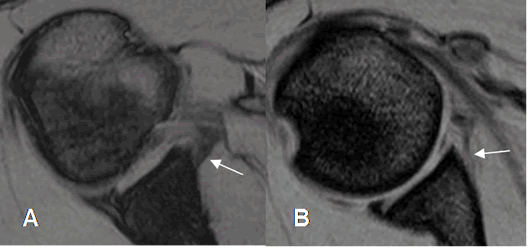

Fig 63. Lesión de Bankart.

A: RM axial en FFE y B: ArtroRM axial. Signos de lesión de Bankart, que se confirma en la ArtroRM. (Flecha delgada). Adicionalmente hay ruptura del LGH medio. (Flecha gruesa).